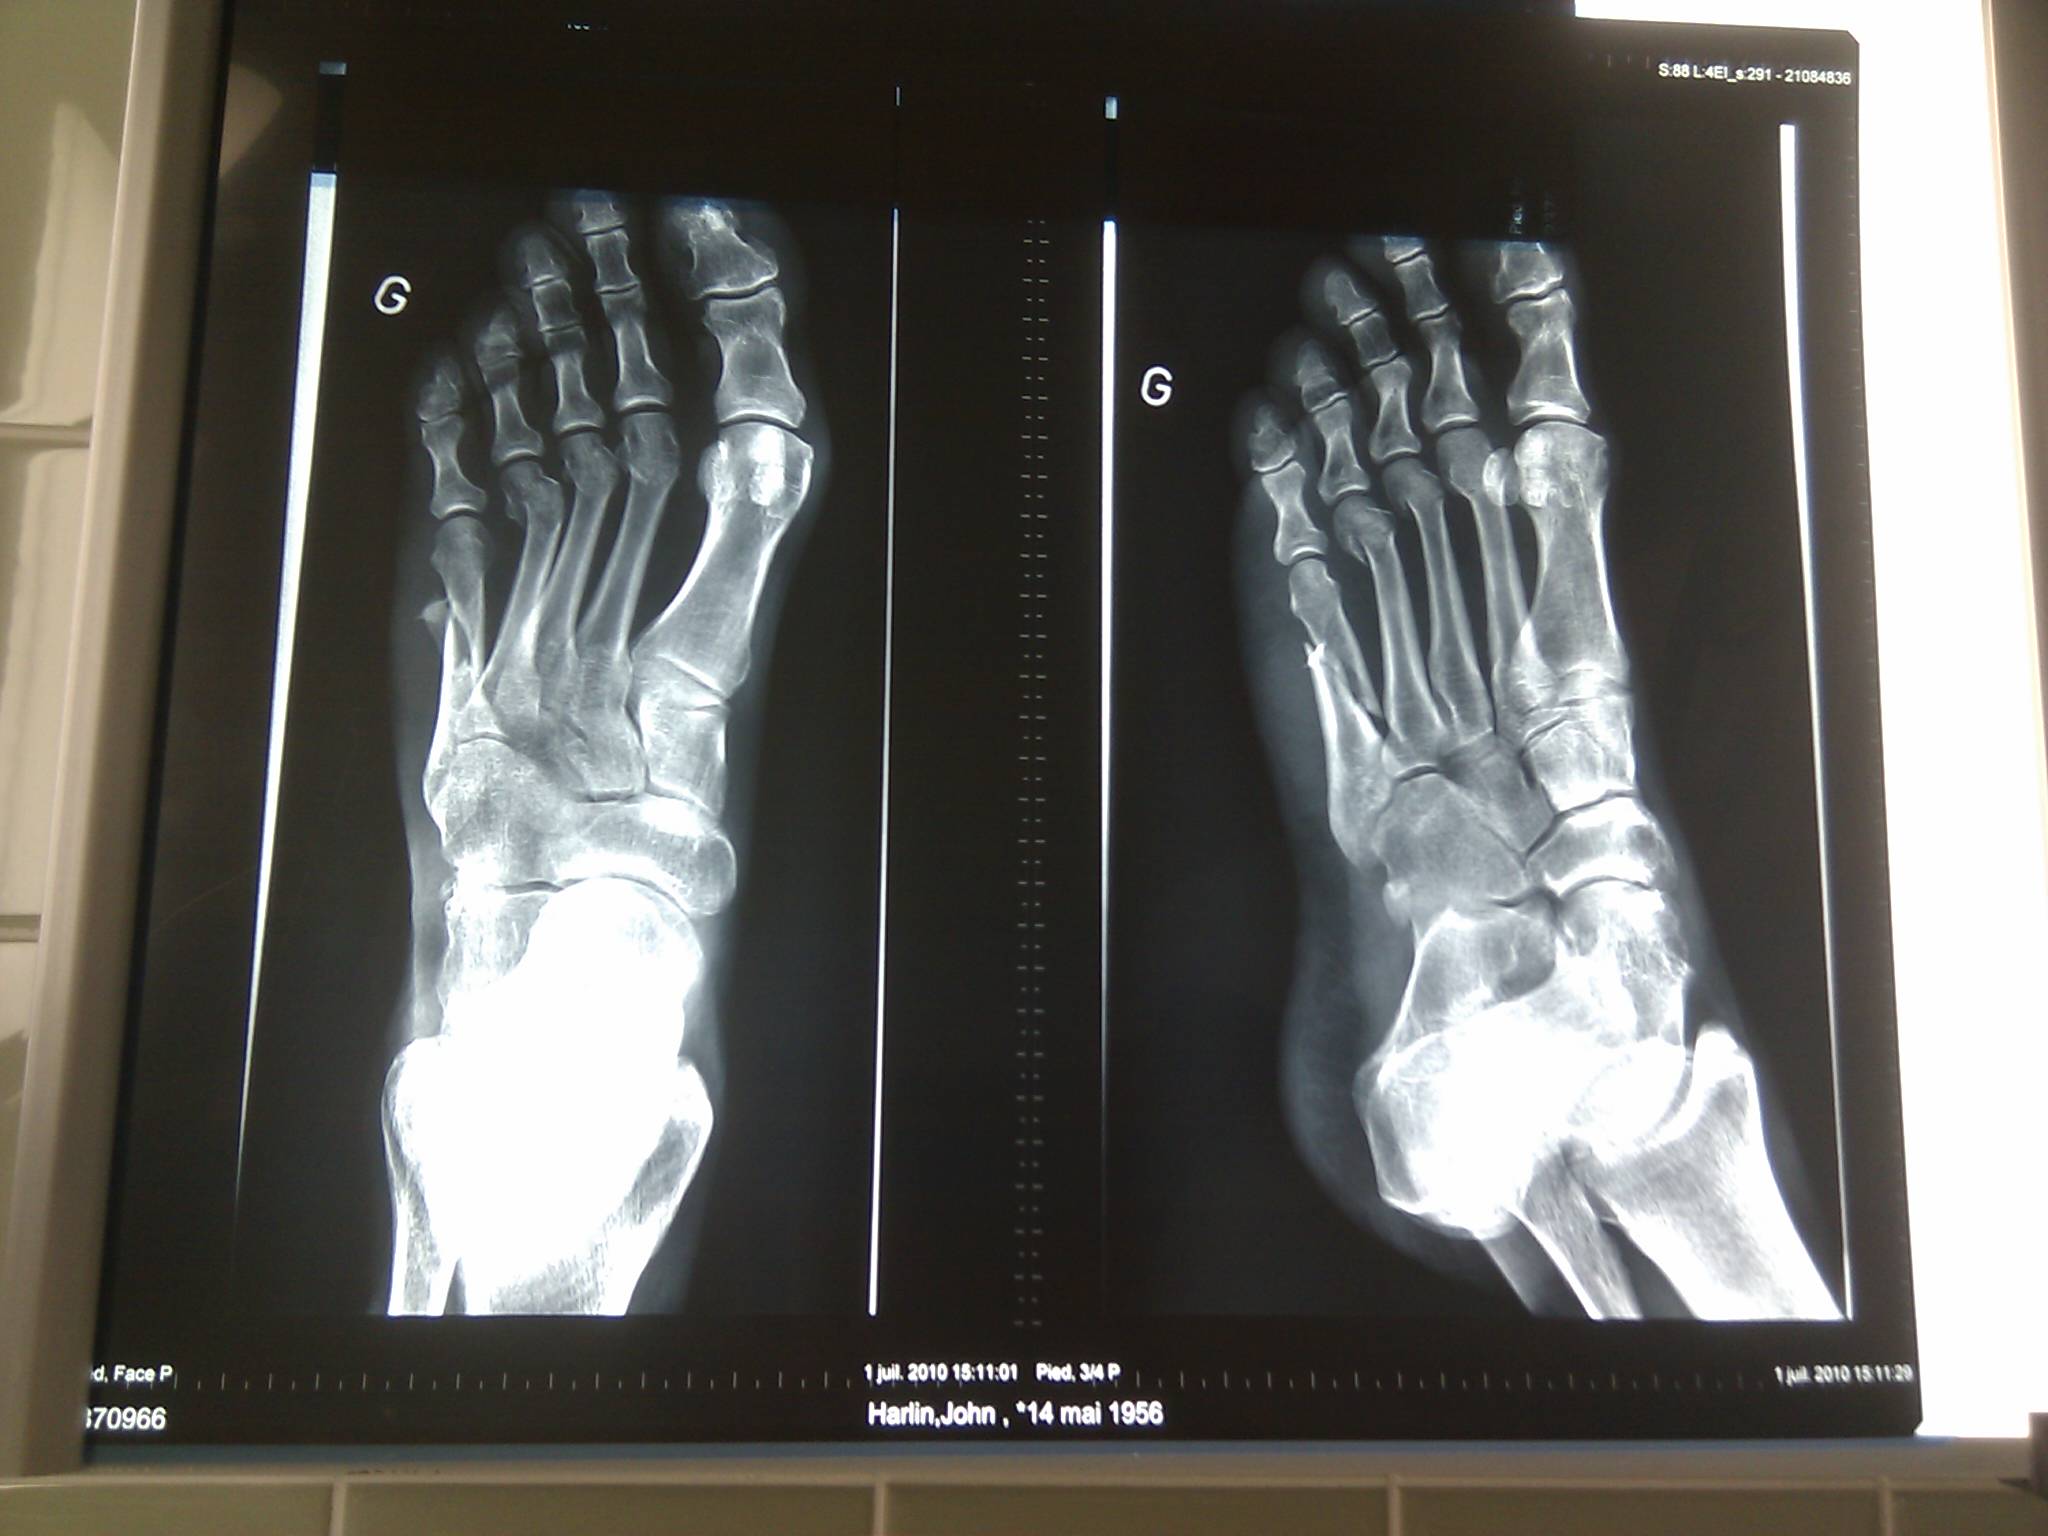

アメリカ人作家で冒険家のハーリン氏は、6月22日徒歩でスイスの国境を辿り始めた。9日後に不運に襲われ、山から転落したときに両足の骨を骨折した。回復したハーリン氏は旅を再開した。